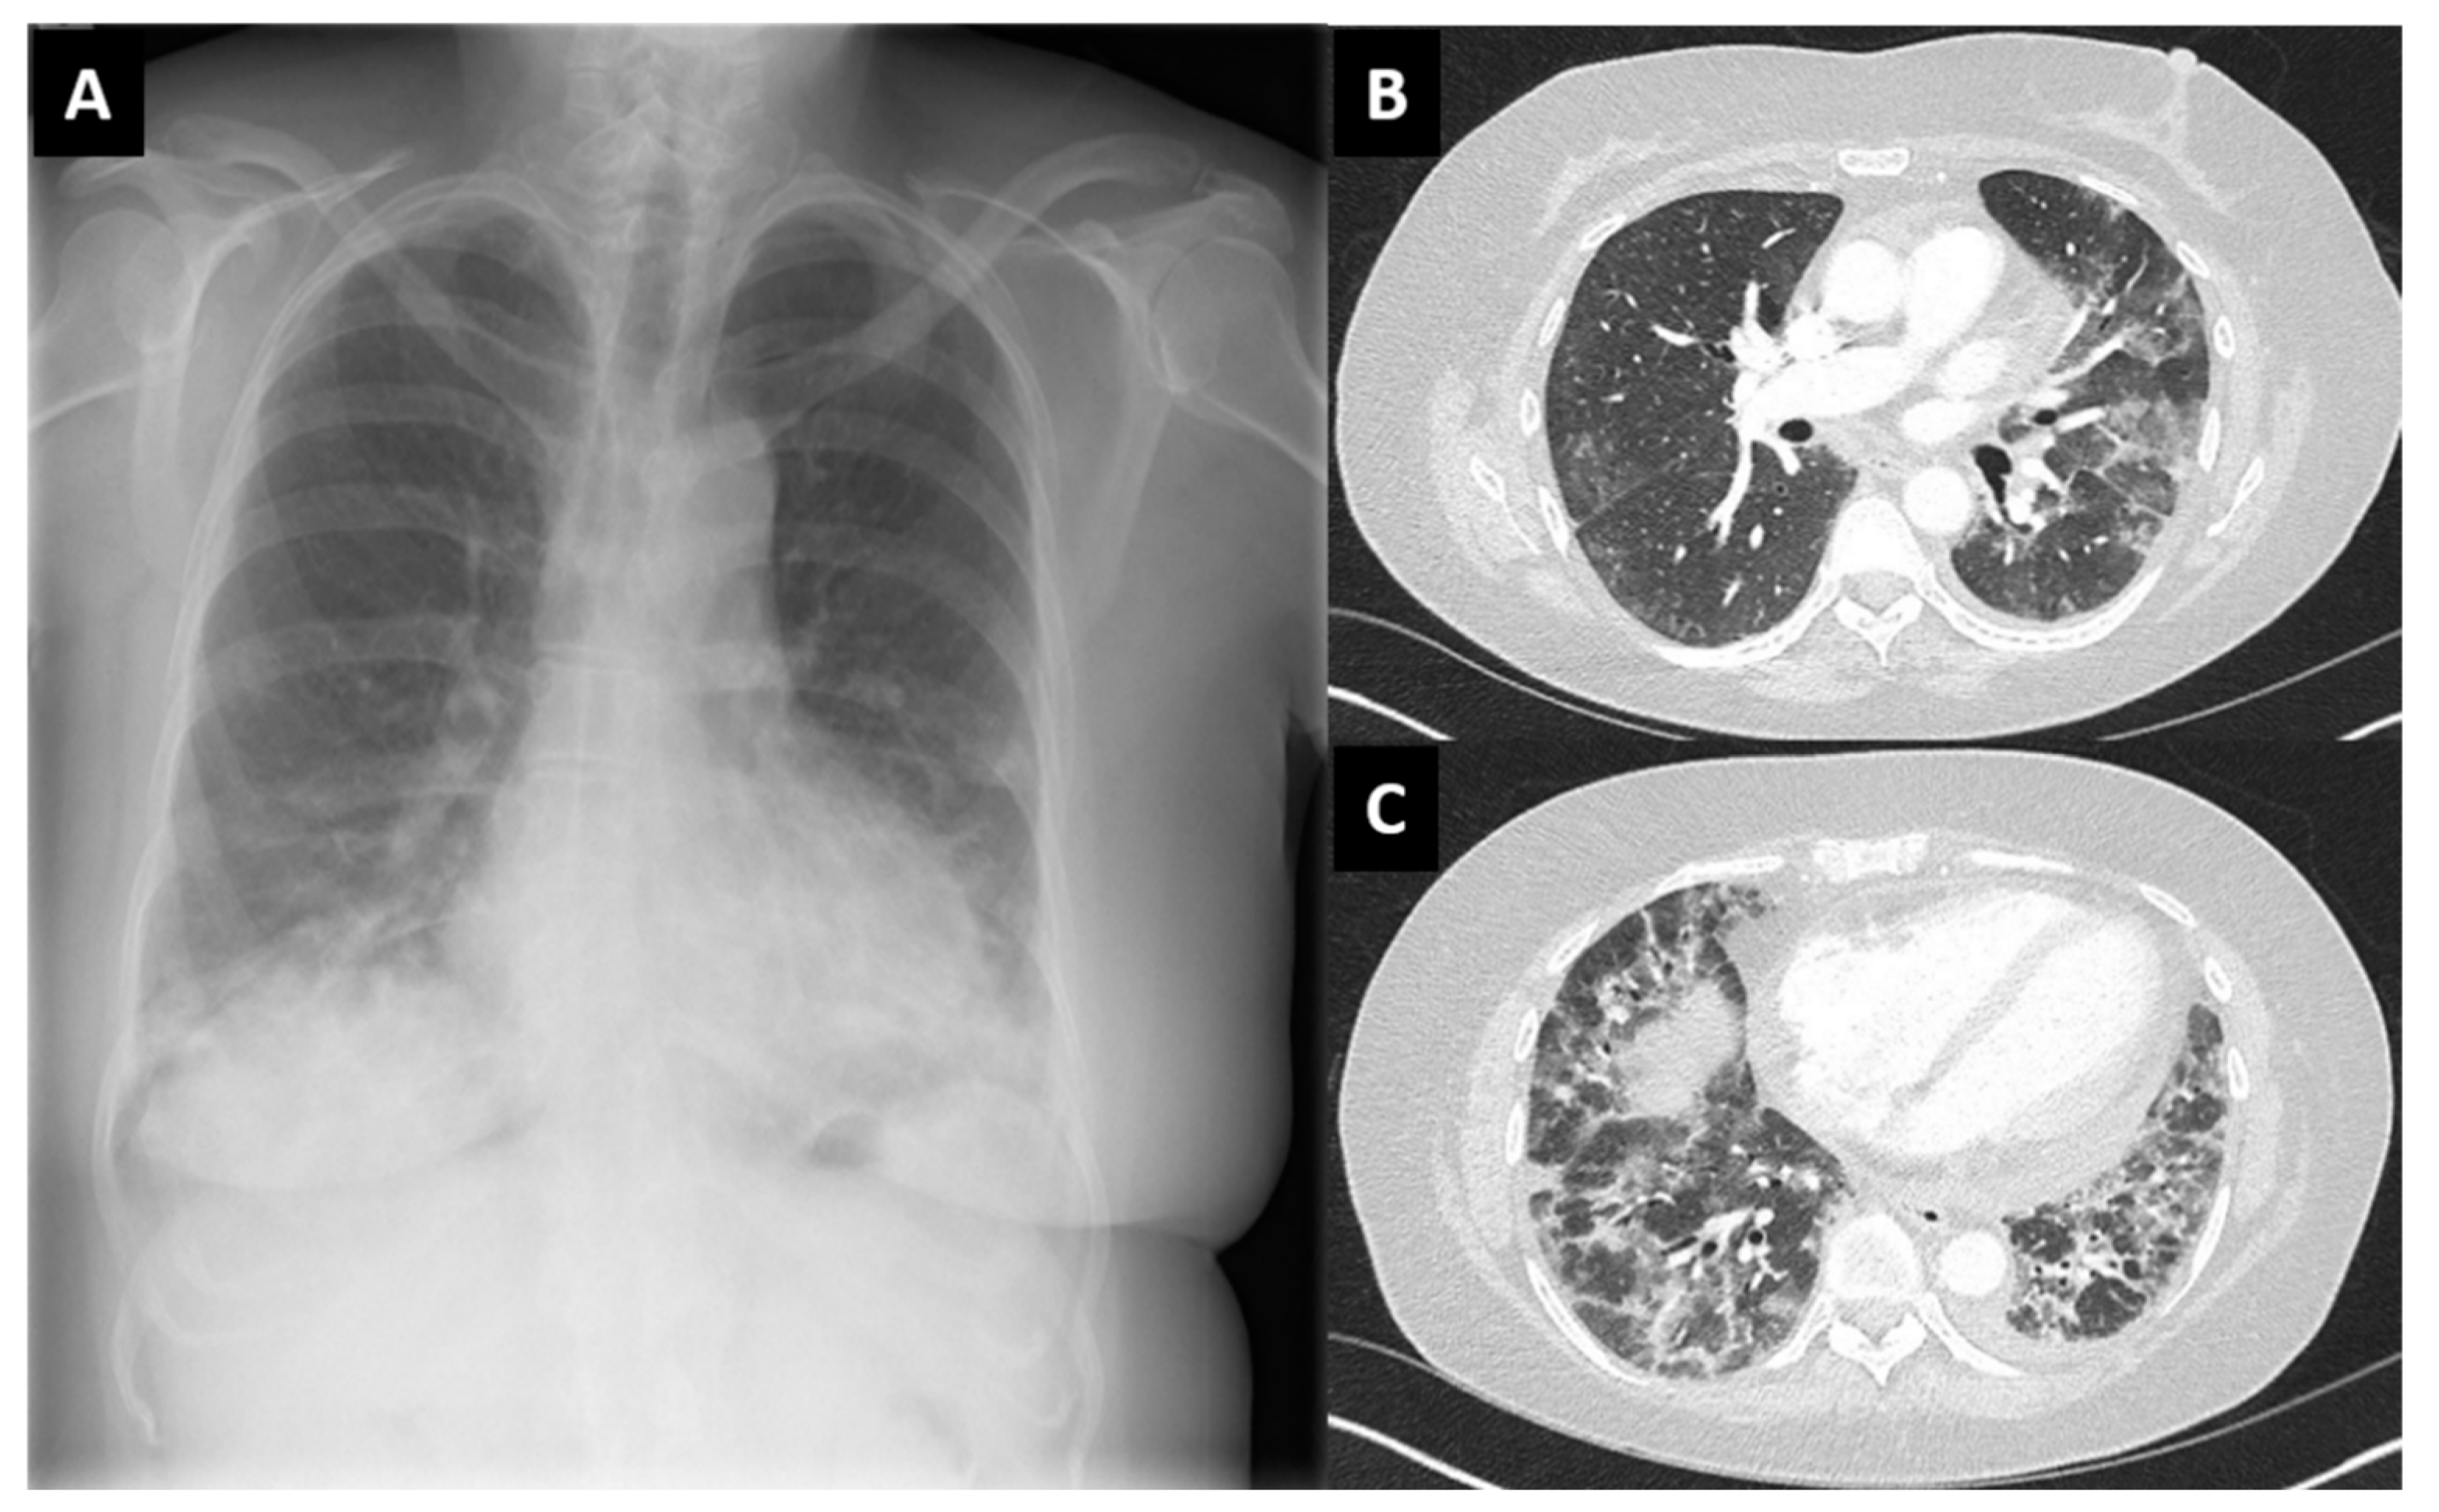

| Case 3 | No | AZD1222/ChAdOx1 | Amyopathic, sicca symptoms, shortness of breath. CRP 20 mg/L, CK normal. ANA + Myoblot + (SL 75, Ro52) | Heliotrope rash, mechanics hands. Interstitial lung disease. Pericardic effusion | Oral steroids, then IV cyclophosphamide followed by mycophenolate |

| York | dose 1, May 2021 | ||||

| Female, 58 | (4 weeks) | ||||

| Case 5 | No | BNT162b2 | CK 4793 U/L, CRP 55 mg/L. Anti-Jo1 + (>8.0 U/L) Ro52 1.00 (cut-off = <0.99) | Usual interstitial pneumonia (cataract, iatrogenic) | Oral steroids |

| Harrogate | Dose 3, September 2021 | ||||

| Male, 82 | (4 weeks) | ||||

| Case 10 | No | BNT162b2 | Asthenia. CK 3581 U/L, CRP 109 mg/L, myositic pattern on EMG, muscle oedema on MRI, biopsy positive ANA negative, Myoblot negative Anti-HMGCR + | Mild interstitial changes on computed scan, asymptomatic | IV, then oral steroid Methotrexate |

| Mid-Yorkshire | Dose 3, October 2021 | ||||

| Female, 71 | (5 weeks) | ||||